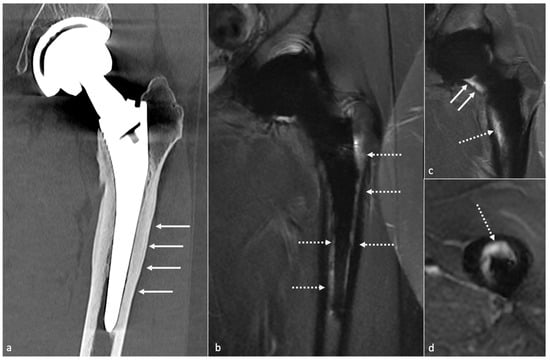

4.10. Peri-Prosthetic Fractures and Stress Reactions

4.10.2. Imaging